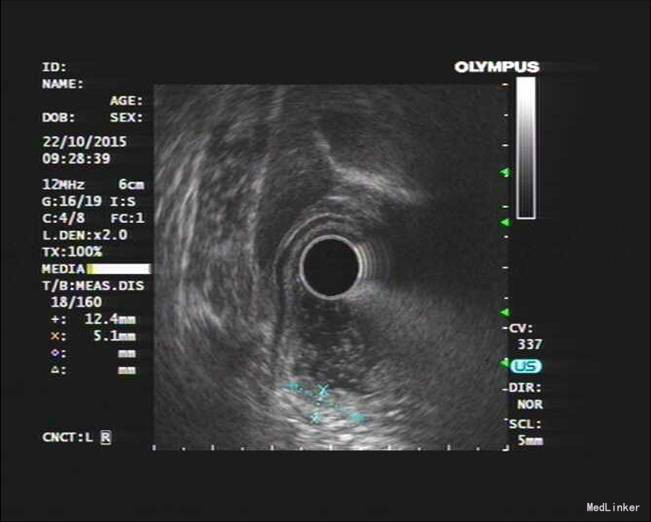

患者,男性,69岁,间歇性中上腹隐痛1月,加剧1周来我院门诊就诊,胃镜检查:见胃窦前壁处可见一1.5*2.0cm粘膜隆起,表面粗糙,见图1,胃镜诊断:胃窦粘膜隆起(性质待病理),慢性浅表性胃窦炎伴胆汁反流,10月26日门诊病理:胃窦:慢性萎缩性胃炎,急性活动,伴部分腺体中重度不典型增生,局灶重度不典型增生。于2015年10月28日入院。

诊疗经过:入院后经过术前检查,行放大内镜检查和超声内镜检查,超声内镜提示:胃窦病灶未突破粘膜下层,诊断考虑:胃早癌。于10月30日行内镜下胃ESD术,术顺,安返病房。经过过制酸、补液等对症处理,3天后患者顺利出院。

随访:出院后2周,电话随访患者,一般情况良好,无不适主诉。 讨论:该患者胃镜见一胃窦前壁粘膜隆起,表面粘膜粗糙,病理示:慢性萎缩性胃炎,伴部分腺体中重度不典型增生,局灶重度不典型增生,超声胃镜病灶未突破粘膜下层,有胃ESD手术指征,故行全麻下胃ESD术。术后病理:胃窦前壁肿瘤:腺上皮高级别上皮同瘤,部分癌变,病变大小1.5*1.1*0.3cm,基底及切缘未见癌。说明手术成功,切缘及基底均无肿瘤侵及。对于早癌患者我们完全可以通过采用ESD方法治愈患者,胃镜下切除早癌较腹腔镜创伤更小。我和患者解释时是这样说的:腹腔镜是微创,而我们内镜下ESD则是微微创。